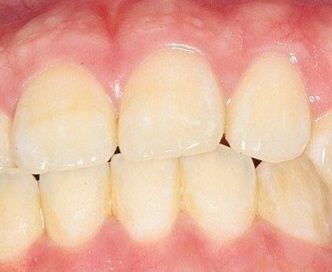

식사를 하거나 일상생활에서 교합을 하는데 큰 문제가 없다면 정상교합으로 판단합니다.

피개량이 적긴하지만 위에 치아가 아래 치아를 덮고 있다면 반대교합이나 절단교합이 아닌 정상교합의 범주에 있다고 판단을 하게 됩니다.